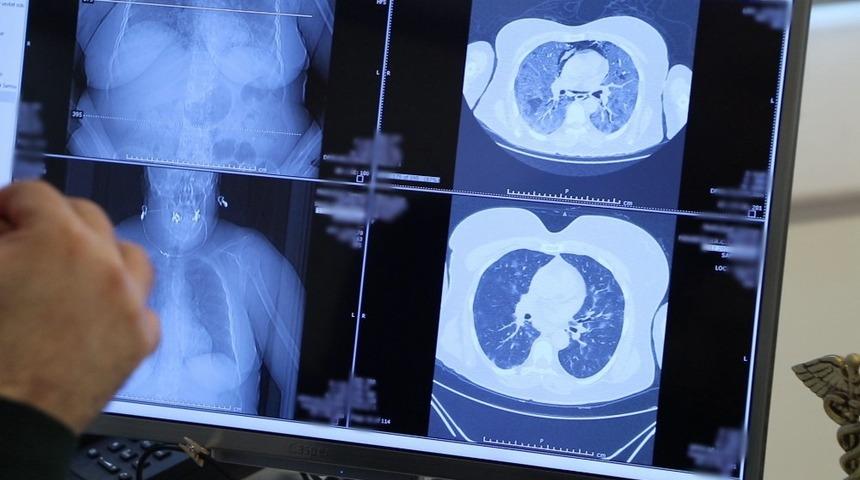

İngiltere’de koronavirüsün mutasyona uğramış hali tespit edildi. VM Medical Park Samsun Hastanesi’nde görev yapan ve şu ana kadar binlerce koronavirüs hastasının şifa bulmasını sağlayan Göğüs Hastalıkları Uzmanı Prof. Şevket Özkaya, mutasyona uğramış virüs hakkında açıklamalarda bulunarak koronavirüsü ağır geçirmiş bir evli çiftin akciğerleri üzerinden örnekler verdi. Çocuklarından koronavirüs bulaştığı öğrenilen evli çiftin ilk iki gün hafif seyredilen hastalıklarının birkaç gün içinde yaygın solunum yetmezliğine dönüştüğü belirlendi. İncelediği akciğerlerin ve verdiği vaka örneğinde direkt temasın, bulaşıcılığı ve hastalığı çok hızlı ilerlettiğini gösterdiğine dikkat çeken Prof. Dr. Şevket Özkaya, “Örnek vermek gerekirse, bir karı-kocanın çocuklarının ikisi de pozitif olan ama genç oldukları için akciğerleri tutulmamış ama genç-taşıyıcı olduğu için anne ve babalarına bulaştıran aile içindeki gözlemlenen vakayı size paylaşacağım. Bu kadın hastamızda, kızından aldığı virüs nedeniyle oluşan çok hafif pulmoner akciğer tutulumu şikâyeti birkaç gün içerisinde hızla ilerliyor ve yaygın solunum yetmezliği ortaya çıkıyor. Bu vaka, direkt temasın çok hızlı bulaşıcılığını ve hastalığın çok hızlı ilerlediğini gösteriyor. Hastamızın eşine baktığımızda da yine kızından bulaşan virüsle akciğerinde hafif bir tutulma olduktan sonra çok hızlı bir şekilde ilerleyip hastaneye yatacak düzeyde bir nefes darlığı ortaya çıktığını gördük. Halkın mutasyona uğrayan koronavirüsüyle ilgili bilmesi gereken iki nokta var. Birincisi mutasyonlu virüs çok hızlı şekilde bulaşabilir, çünkü bulaştırıcılığı çok fazla. İkincisi de tedaviye rağmen düzelme görülemeyebilir ama bu mutasyon olduğunu göstermez” diye konuştu.